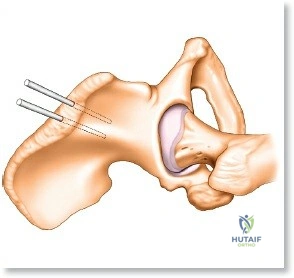

Humerus External Fixation

Humeral external fixation is most frequently utilized for damage control in polytrauma or for severe open fractures.

Proximal Humerus Pin Placement

1. Identify the safe zone on the lateral aspect of the proximal humerus, distal to the axillary nerve.

2. Make a longitudinal incision over the lateral aspect of the greater tuberosity or proximal diaphysis.

3. Bluntly dissect through the deltoid muscle fibers down to the bone.

4. Insert the drill sleeve, pre-drill with a 3.5 mm or 4.0 mm bit, and insert a 5.0 mm half pin.

5. Confirm bicortical purchase with fluoroscopy.

Distal Humerus Pin Placement

1. The distal pins are typically placed posteriorly to avoid the radial nerve.

2. Make a longitudinal incision over the posterior aspect of the distal humerus, proximal to the olecranon fossa.

3. Split the triceps bluntly down to the periosteum.

4. Insert the tissue protector, pre-drill, and place the 5.0 mm pins from posterior to anterior.

5. Ensure the pins do not penetrate the anterior cortex excessively to avoid injury to the brachial artery or median nerve.

Construct Assembly

Connect the proximal and distal pins with pin-to-bar clamps and an 11 mm carbon fiber rod. Reduce the fracture under fluoroscopic guidance using manual traction. Tighten the clamps to secure the reduction. A biplanar construct can be created by adding anterior pins proximally and connecting them to the primary frame.